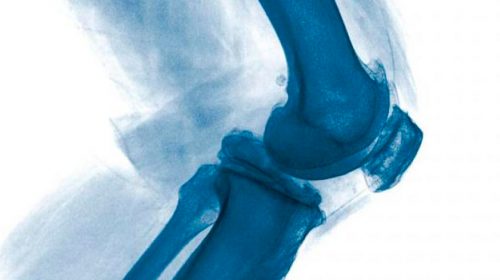

Сергієнко Р. О. – лікар-ортопед-травматолог вищої категорії, кандидат медичних наук. Є провідним фахівцем клініки. Доктор одним з перших в Україні почав займатися артроскопією колінного, плечового і тазостегнових суглобів. Має найбільший досвід в Україні в напрямку артроскопії плечового суглоба. Доктор здійснив тисячі успішних операцій.

- Консервативне лікування патології колінного та плечового суглобів з використанням нових технологій і ультразвукової навігації;

- Всі види артроскопічних операцій на плечовому та колінному суглобах;

- Складні реконструктивні операції, включаючи остеотомії.

- Перший в Україні впровадив артроскопічні операції (через декілька проколів на шкірі) плечового, колінного та кульшового суглобів в широку практику;

Артроскопія колінного суглоба